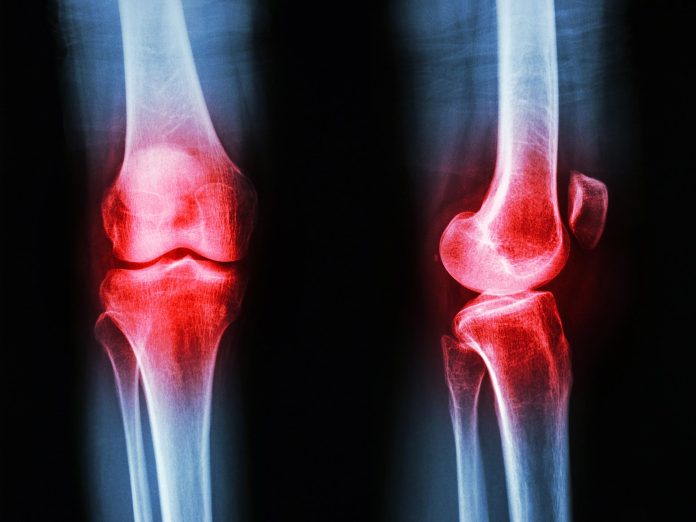

Οι ερευνητές ανακάλυψαν μια απαρατήρητη μέχρι τώρα παρουσία της ορμόνης GLP-1 στις αρθρώσεις ασθενών με αρθρίτιδα. Η αρθρίτιδα δεν είναι μια μεμονωμένη ασθένεια αλλά μια ευρεία κατηγορία διαταραχών των αρθρώσεων που περιλαμβάνει αυτοάνοσες παθήσεις όπως η ρευματοειδής αρθρίτιδα και η ψωριασική αρθρίτιδα, καθώς και εκφυλιστικές ασθένειες όπως η οστεοαρθρίτιδα. Παρά τις διαφορές τους, πολλές μορφές έχουν κοινά […]